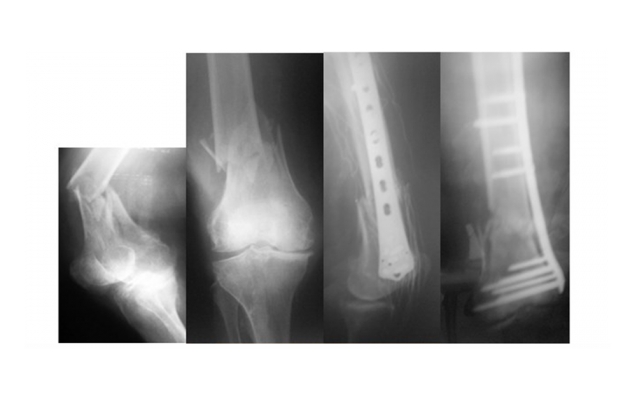

Κάταγμα καλείται η μερική ή ολική λύση της συνέχειας του οστού. Για να γίνει ένα κάταγμα,πρέπει να επιδράσει πάνω στο οστού σημαντική βία. Πολλές φορές όμως προκαλούνται κατάγματα από ασήμαντη βία σε οστού που παρουσιάζει κάποια παθολογία (κύστη, όγκος, οστεοπόρωση κτλ) (παθολογικά κατάγματα). Άλλοτε πάλι, κατάγματα προκαλούνται από μικρής έντασης βίας, η οποία δρα πολλές φορές πάνω σε ένα φυσιολογικό οστό και η οποία εάν επιδρούσε μία φορά, δε θα προκαλούσε κάταγμα (κατάγματα κοπώσεως).